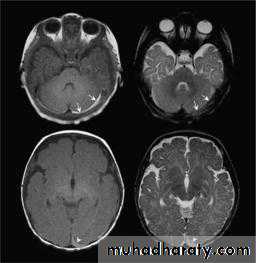

FixedWhen reviewing an MR image, the easiest way to determine which pulse sequence was used, or the "weighting" of the image, is to look at the cerebrospinal fluid (CSF). If the CSF is bright (high signal), then it must be a T2-weighted imaged. If the CSF is dark, it is a T1-weighted image.

Less tissue contrast compared to MRI

Much higher detail in the soft tissues